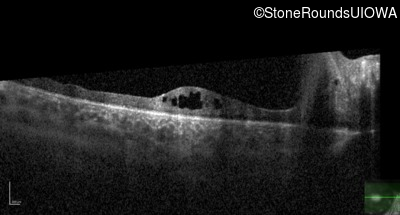

XL Retinoschisis (IIIB1)

Age at visit: 3 years

This 3 1/2 year old boy was noted to have a right esotropia 1 year earlier.

Diagnosis & molecular findings

Disease Gene Allele 1 variant(s) Allele 2 variant(s) Inheritance mode

XL Retinoschisis RS1 Ser221 Ins1aG   XL